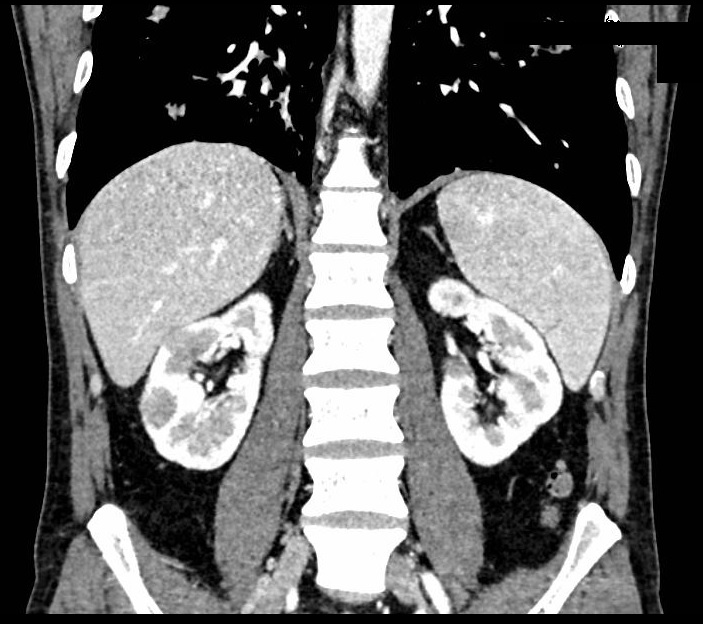

Case presentation: A 39-year-old man was initially diagnosed with lung cancer based on computed tomography and histopathologic findings. He was treated with 2 lines of chemotherapy over an 8-month period, the neoplastic lung lesions progressed, and he was referred to palliative care. Two years after his initial diagnosis, during the management of an actively bleeding gastric tumor, he was diagnosed with HIV and referred to an infectious disease unit. Immediate antiretroviral treatment was initiated after diagnosis, and further evaluation confirmed the presence of B-cell lymphoma. A retrospective review suggested that the initial cancer diagnosis was likely misinterpreted and was in fact lymphoma, a malignancy commonly associated with HIV. Lymphoma treatment was initiated, and after 1 year, the patient achieved HIV-1 virologic suppression and near-complete remission of all lesions.